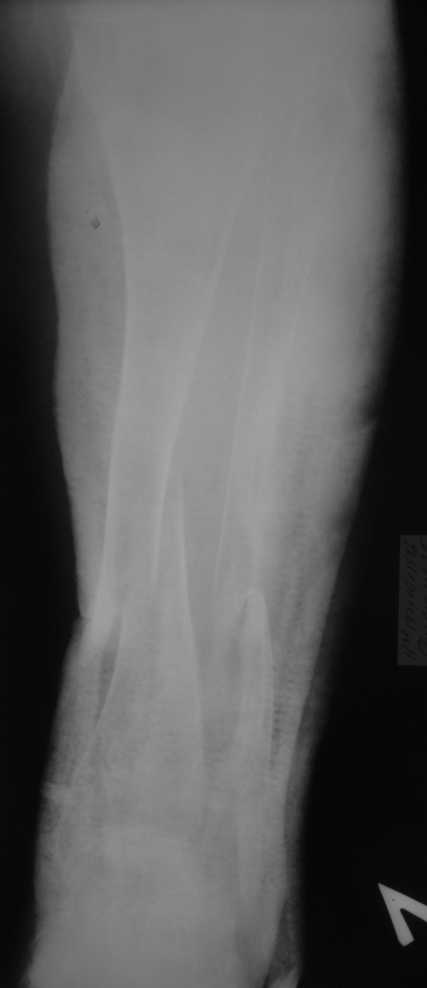

Re: Множественные переломы нижних коенечностей на фоне деформаций

Но даже при малоинвазивной методике лечения применимой для даной больной существуют следующие проблемы: выраженный остеопороз, тонкий кортикал, очень широкий канал.

Контрольные рентгенограммы прилагаю.